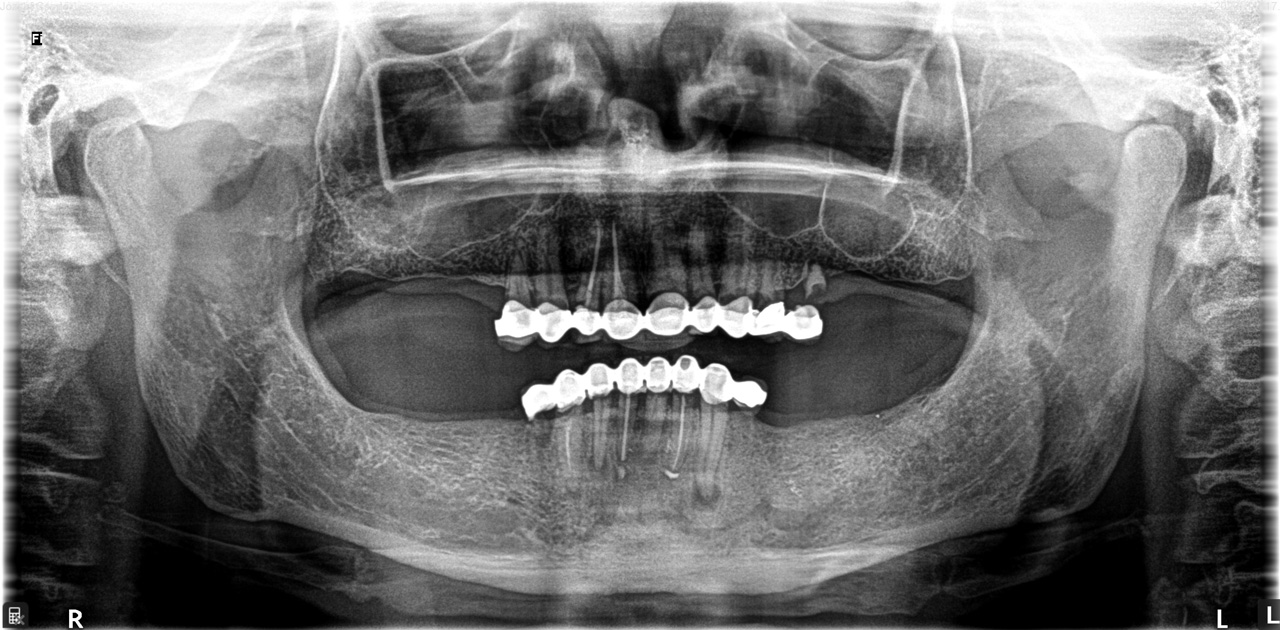

2 nap alatt varázsoltuk ezt a szép esztétikus alsó, felső körhídat implantátumokkal megtámasztva a korábban elhanyagolt szájba. Az 1. nap 26 fogat távolítottunk el, mert annyira rossz állapotban voltak, és rögtön azonnal terhelhető IHDE svájci implantátumokat raktunk be, fentre 8, lentre 6 darabot. A sebeket összevarrtuk és intraorális szkennerrel digitális lenyomatot vettünk. 2 nap múlva pedig beragasztottuk a kész PMMA műanyag körhidakat. Dr. Kelemen Péter és a Symbion Fogtechnika munkája.

Teljes fogatlanság helyreállítása 2 nap alatt

Teljes fogatlanság helyreállítása 2 nap alatt azonnal terhelhető svájci IHDE implantátumokkal és PMMA műanyag hidakkal. Intraorális szkennerrel vettünk lenyomatot az implantáció után, és erre a digitális mintára készítette el a fogtechnika a hidak digitális tervezését, majd faragta ki műanyagból. Ezt a gyors munkát az azonnal terhelhető implantátumok és a digitális lenyomat, tervezés segítségével tudtuk megcsinálni mindössze 2 nap alatt. Dr. Kelemen Péter és a Symbion Fogtechnika munkája.